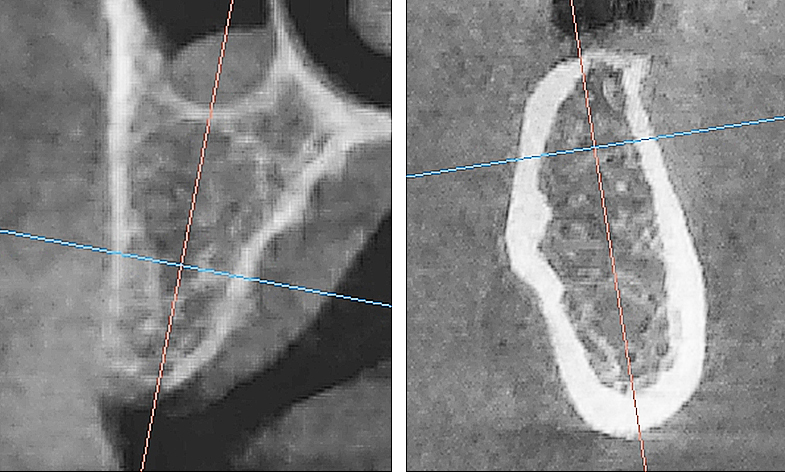

Рис. 2. Поперечный срез альвеолярной кости верхней челюсти человека в проекции отсутствующего премоляра (А) и альвеолярная кость нижней челюсти человека в проекции отсутствующего моляра (Б). 3D-КЛКТ

Учитывая выше перечисленные недостатки, поиск новых областей и способов хирургического доступа для создания экспериментальной модели исследования остеопластических материалов является актуальным. Нас заинтересовало использование в качестве экспериментальной живой модели область локтевого отростка передних конечностей овцы. В доступной литературе нами не встречено упоминаний об использовании локтевых отростков овец с целью формирования костных дефектов для оценки регенераторного потенциала остеопластических материалов. Вероятно, это обусловлено боязнью риска травматизма локтевого отростка в ходе формировании дефекта при использовании классического хирургического инструментария – сверл и фрез большого диаметра. Между тем очевиден ряд преимуществ данной области – схожее анатомическое строение и архитектоника с альвеолярной частью челюстей человека. Локтевой отросток имеет наружный кортикальный слой и внутренний, представленный губчатым веществом с костномозговыми пространствами небольшого размера (рис. 1, 2).